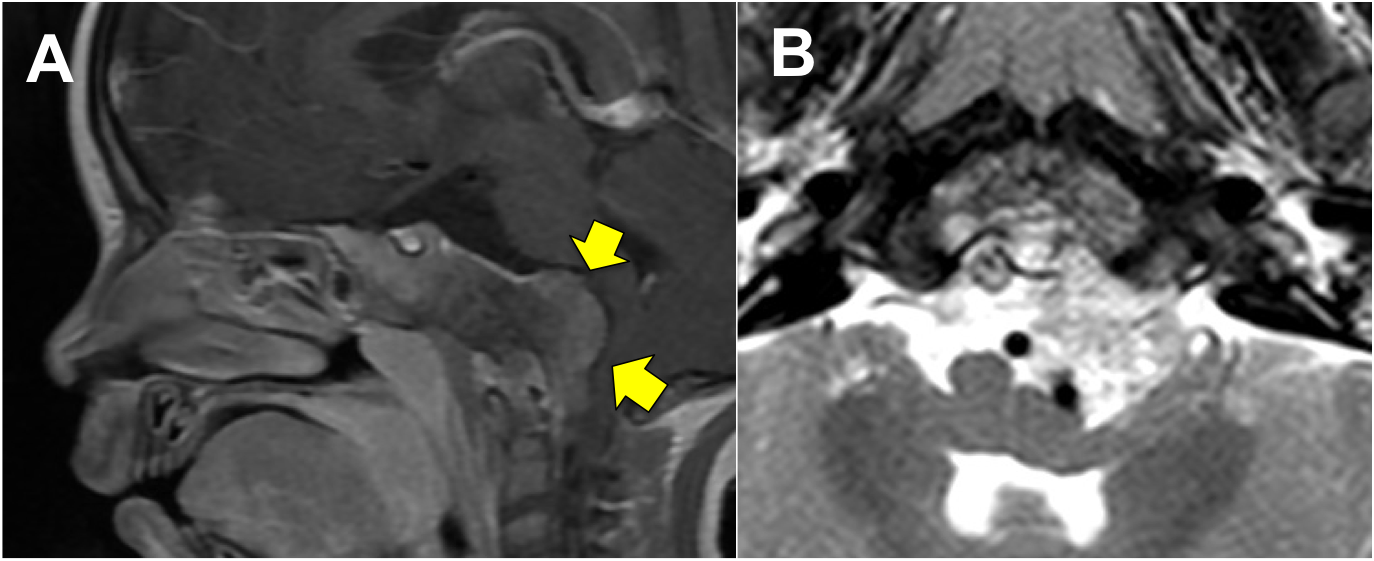

Introducción: La cirugía endoscópica endonasal se ha convertido en una herramienta fundamental para el manejo de patologías que comprometen la base de cráneo. En casos bien seleccionados, estas técnicas permiten resecciones quirúrgicas con una menor morbilidad sin comprometer los principios oncológicos de resección. Con el desarrollo de instrumental especializado, nuevas tecnologías y la experiencia de los cirujanos, la cirugía endoscópica endonasal se usa cada vez más en cirugía de base de cráneo en niños.

Resultados: Fueron intervenidos 8 pacientes entre los 2 y 14 años, con una edad promedio de nueve años y un seguimiento promedio de 16 meses. En el 75% se hizo una resección total del tumor. Un paciente requirió una reintervención y un paciente fue sometido a radiocirugía post-operatoria. 1 paciente falleció a pesar de múltiples intervenciones, quimioterapia y radioterapia.

Conclusión: La cirugía endoscópica endonasal para tumores de base de cráneo puede ser utilizada de forma segura en los pacientes pediátricos, es una técnica que en casos bien seleccionados pueden ofrecer excelentes resultados disminuyendo la morbilidad y complicaciones de las técnicas abiertas.